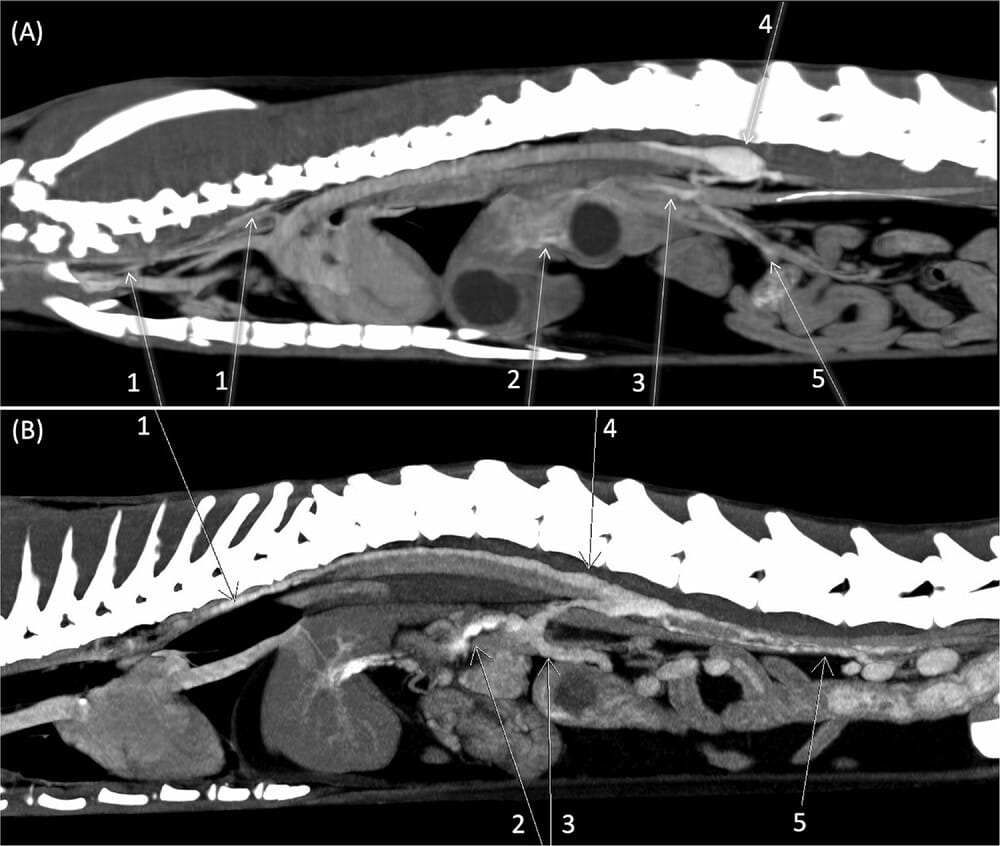

Sagittal reconstruction from delayed post-contrast intravenous series showing diffuse enhancement of the lymphatic system in two feline patients (A, B). A, Images acquired with 16-row MDCT unit (Siemens Emotion 16) (Slice thickness 1,5 mm; WW 402; WL 109). 1- thoracic duct; 2- hepatic lymph vessels; 3- celiac trunk; 4- cisterna chyli; 5- mesenteric lymph vessels. B, Images acquired with Dual-source CT 192 × 2 (Siemens Somatom Force) volume rendered (Slice thickness 0,6 mm; WW 300; WL 40). 1- thoracic duct; 2- celiac trunk; 3- mesenteric trunk; 4- cisterna chyli; 5- lumbar trunks.